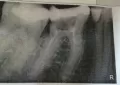

Три дня назад мне удалили нерв, поставили штифт и временную пломбу пока не сделаю снимок, и врач не убедится, что все в порядке. Зуб нижняя шестерка.

Я не могу Вам ничего сказать без рентген-снимка. Депульпация зуба сопровождаемся как минимум 2-3 рентген-снимками. В Вашем случае нарушен весь протокол лечения. Если врач депульпирует зуб, и при этом не вымеряет длину канала, не контролирует конусность и качество пломбировки, в этом случае ничего хорошего быть не может.